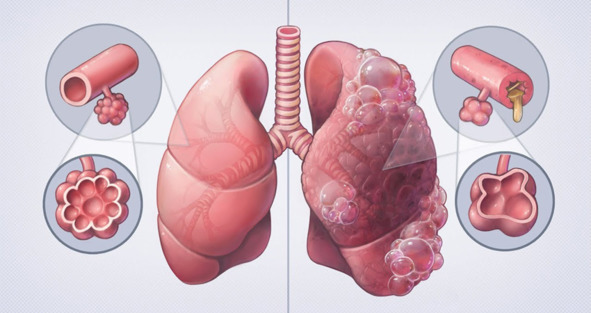

ХОБЛ бывает двух типов:

Как вы видите на рисунке вначале статьи, ХОБЛ бывает эмфизематозный и бронхитический. То, что это не одно и тоже, вы видите по картинке. От врачей я об этом не слышал вообще. Поэтому очень вам советую определить точно какой у вас тип ХОБЛ, хотя бы по внешним признакам, так как для различных типов вам понадобятся различные лекарства. О первом типе ничего конкретного не скажу, так как болею вторым типом, при котором вы свои ребра не увидите, а вот в весе прибавите до 30—40 кг и живот «пивной» появится, так что с лишним весом боритесь сразу – лишний вес ВРАГ!

– Бронхитический тип, при котором у больного наблюдается влажный продуктивный кашель, не обусловленный другими заболеваниями. Повышенная масса тела, синюшность (цианоз) кожного покрова говорит о недостаточности кислорода в крови.

– Эмфизематозный тип – расширение капиллярной сети, пониженная масса тела, одышка, межреберные промежутки на стороне поражения втянуты и резко сужены, патологическое расширение внутренних полостей легких, при котором неестественно растягиваются и раздуваются ткани. Возникает так называемый клапанный механизм (воздух легко проникает в ткани, а выходит с трудом).